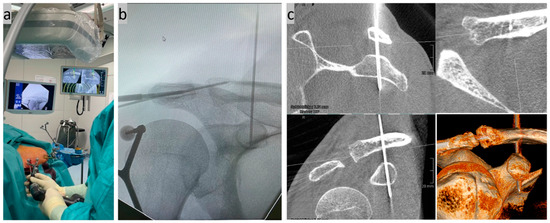

2. Surgical Technique

- Böhringer, A.; Gebhard, F.; Dehner, C.; Eickhoff, A.; Cintean, R.; Pankratz, C.; Schütze, K. 3D C-arm navigated acromioclavicular joint stabilization. Arch. Orthop. Trauma. Surg. 2023, 144, 601–610. [Google Scholar] [CrossRef]